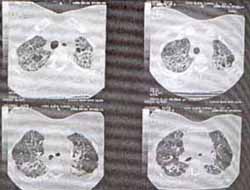

Se inició tratamiento con Estreptomicina, Isoniacida, Rifampicina y Pirazinamida. Un mes después la paciente consulta por persistencia de la anorexia, y empeoramiento de la disnea. Ha perdido 2.5 Kg más de peso, y al examen es evidente ritmo de galope por S3. El cultivo de BK del lavado bronquial y de la biopsia transbronquial fueron negativos. La paciente se hospitaliza y se practica TAC de tórax que demuestra infiltrados intersticiales especialmente hacia los ápices, con formación de bronquiectasias por tracción y áreas de vidrio esmerilado (figura 2). Se realiza biopsia pulmonar a cielo abierto. (Vea también: Ventilación con relación invertida)

Figura No 2. TAC de tórax